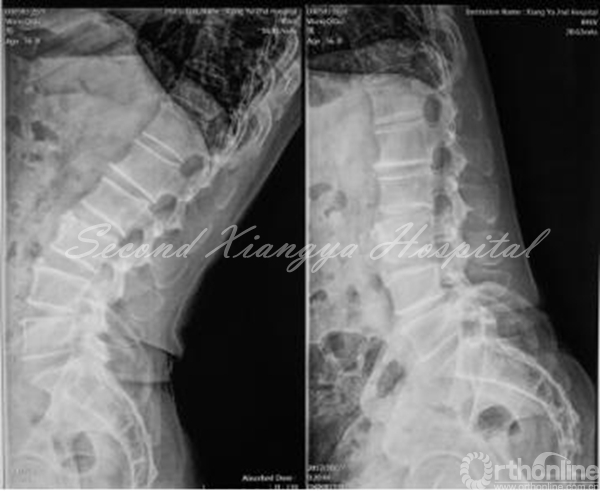

MRI:L4/5椎间盘右侧突出,非游离,无钙化,伴侧隐窝狭窄。

MRI-T2、MRI-T1

MRI-TRANSVERSE